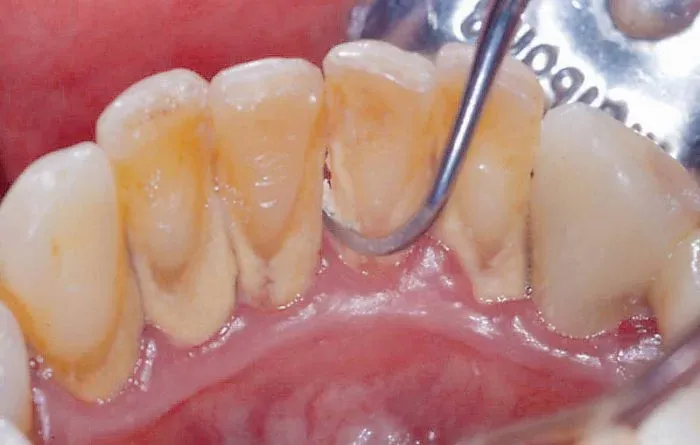

Cao răng (hay còn gọi là tartar, calculus) là những mảng bám cứng, xám hoặc vàng nâu bám chặt vào bề mặt răng, đặc biệt là gần đường viền nướu. Ban đầu, cao răng hình thành từ những mảng thức ăn thừa, vi khuẩn và khoáng chất trong nước bọt tích tụ trên răng. Nếu không được loại bỏ kịp thời bằng cách chải răng và sử dụng chỉ nha khoa thường xuyên, những mảng bám này sẽ dần bị vôi hóa, trở nên cứng và khó loại bỏ hơn rất nhiều.

- Cao răng trên nướu: Loại cao răng này thường có màu vàng hoặc cam, hình thành ở phần răng tiếp xúc với nước bọt và không khí. Cao răng trên nướu thường dễ nhìn thấy và có thể gây khó chịu khi chạm vào.

- Cao răng dưới nướu: Loại cao răng này có màu nâu sẫm hoặc đen, hình thành ở phần răng nằm dưới đường viền nướu. Cao răng dưới nướu khó phát hiện hơn và thường gây ra các vấn đề nghiêm trọng về nướu, như viêm nha chu.